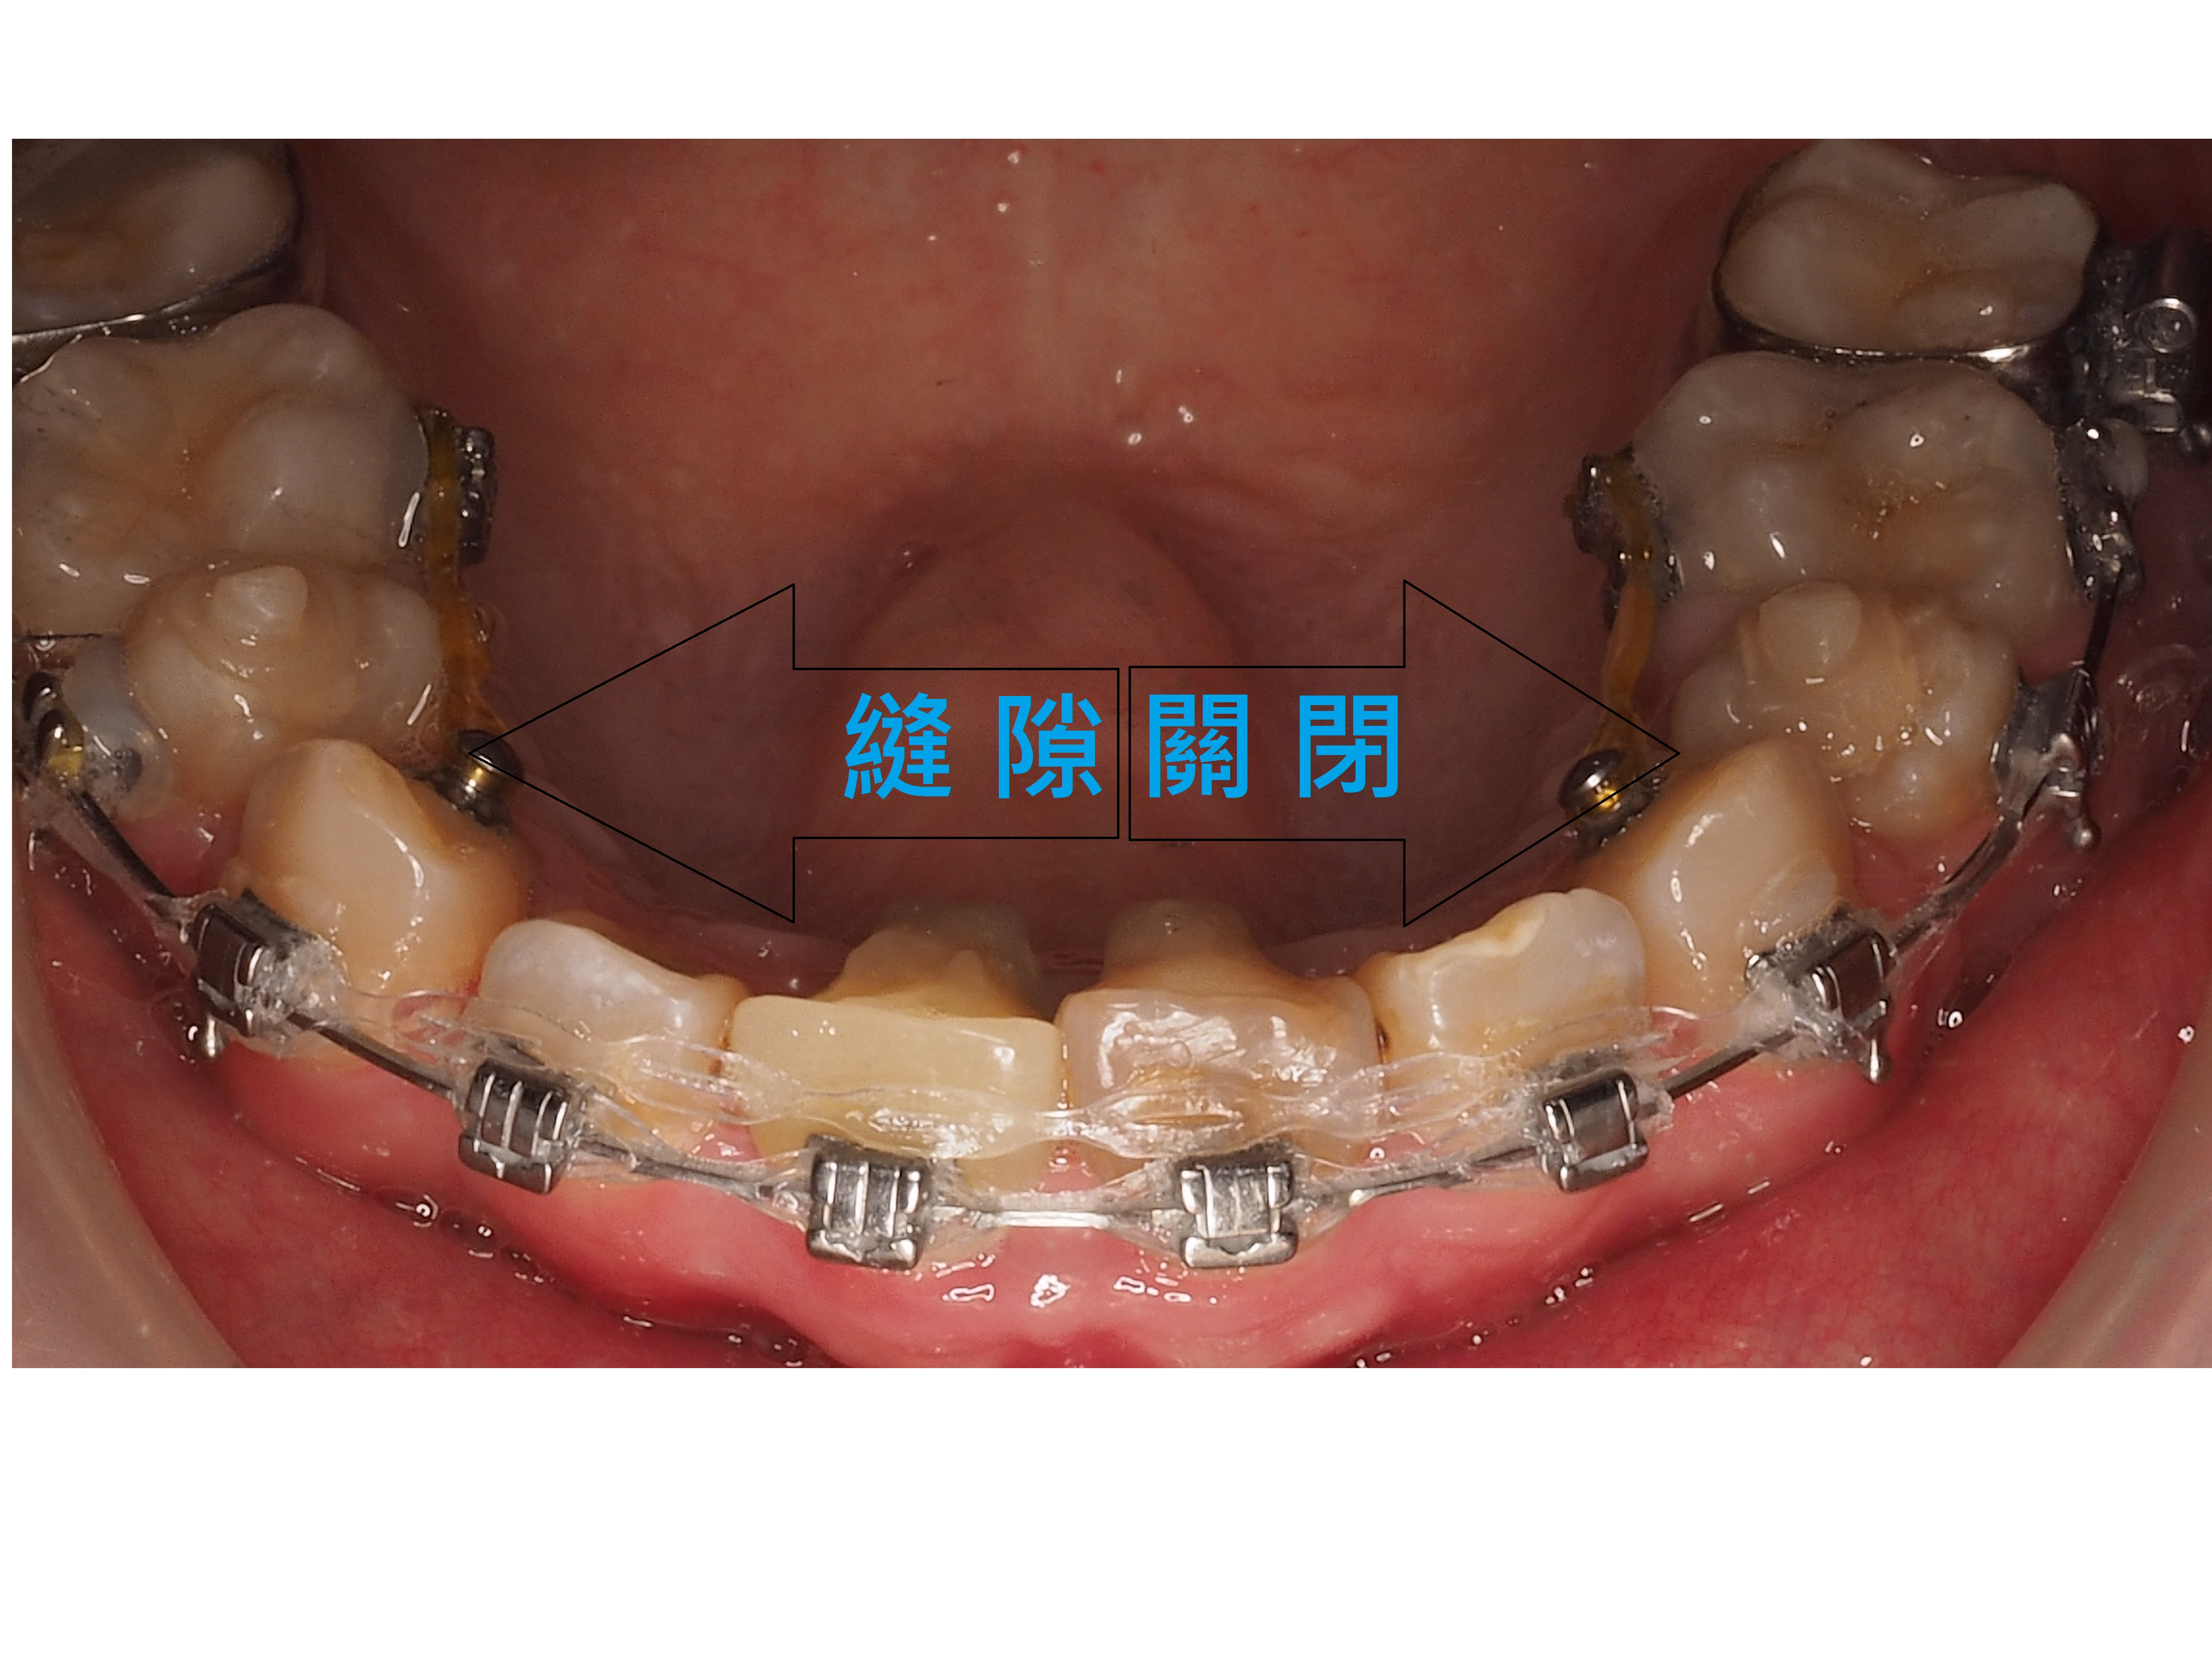

患者陳小姐嘴唇外凸,下門牙分開有一個漏財縫,陳小姐想透過矯正把漏財縫關掉跟改善嘴唇外凸的狀況.

矯正過程中拔掉4顆小臼齒,透過迷你螺絲調整往後拉關縫,讓患者的嘴唇外凸獲得改善,下門牙的漏財縫也關掉了.

Ans:暴牙嘴凸矯正就是前排牙是否有後退空間,當後退空間不足時通常拔牙來製造空間,拔牙加上骨釘配合把牙齒往後退使牙齒排列整齊,最終能改善暴牙與脣形。

Ans:牙齒矯正有分為拔牙與不拔牙兩種方式。

拔牙矯正

一般會拔牙矯正的主要原因是「空間不足」,拔了牙齒才有足夠空間排列整齊。另外還有像是:嘴凸、嚴重暴牙、虎牙較明顯或牙齒排列擁擠不整齊等情況,通常是需要以拔牙的方式進行矯正療程。

不拔牙矯正

不拔牙的矯正則是當空間需求不是那麼大的時候,例如:牙齒間縫隙較大要關縫或輕微凌亂且深咬就比較不需要拔牙。有時並不表示完全不需要空間,可能會藉由修磨牙縫來得到些許空間去做牙齒的移動。